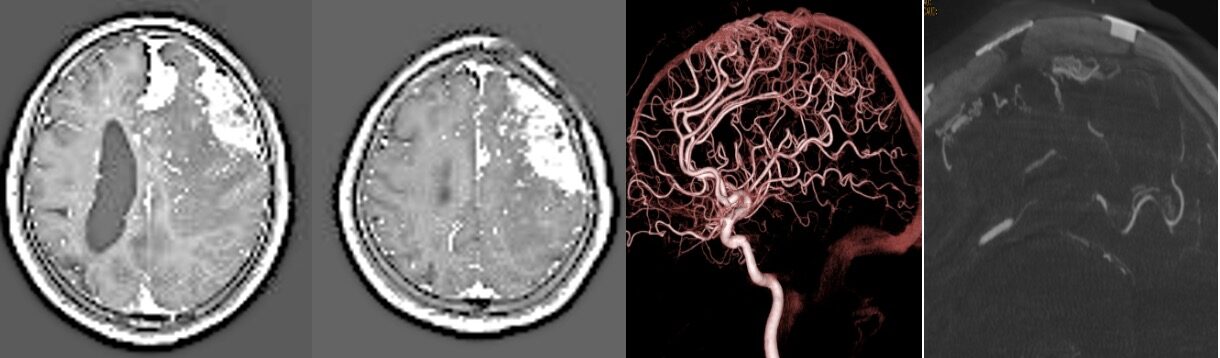

2025年7月 硬膜動静脈瘻を合併した難治性の非典型髄膜腫(再発)に対し開頭治療を行いました。

外来で長期フォローアップを行なっていた左前頭葉髄膜腫に対して手術を一度行い、大きな後遺症なく退院されましたが、組織型が非典型髄膜腫で早期に再発、再増大をきたしました。同時に上矢状静脈洞に硬膜動静脈瘻を生じ、放射線治療や血管内治療を繰り返してきましたが、最終的に難治性てんかんの状態となり、てんかんを繰り返すたびに高次脳機能障害が低下する容易なりました。そのため、開頭によるdAVFシャント離断+髄膜腫摘出+硬膜補填を行いました。手術は極めて長時間を要しり、術中出血も多く困難な手術でした。術後静脈梗塞も生じ、右片麻痺、失語が悪化しました。脳内血腫の消褪とともに少しずつ改善しましたが、まだまだの状態でリハビリ病院に転院しました。回復を祈念しています。